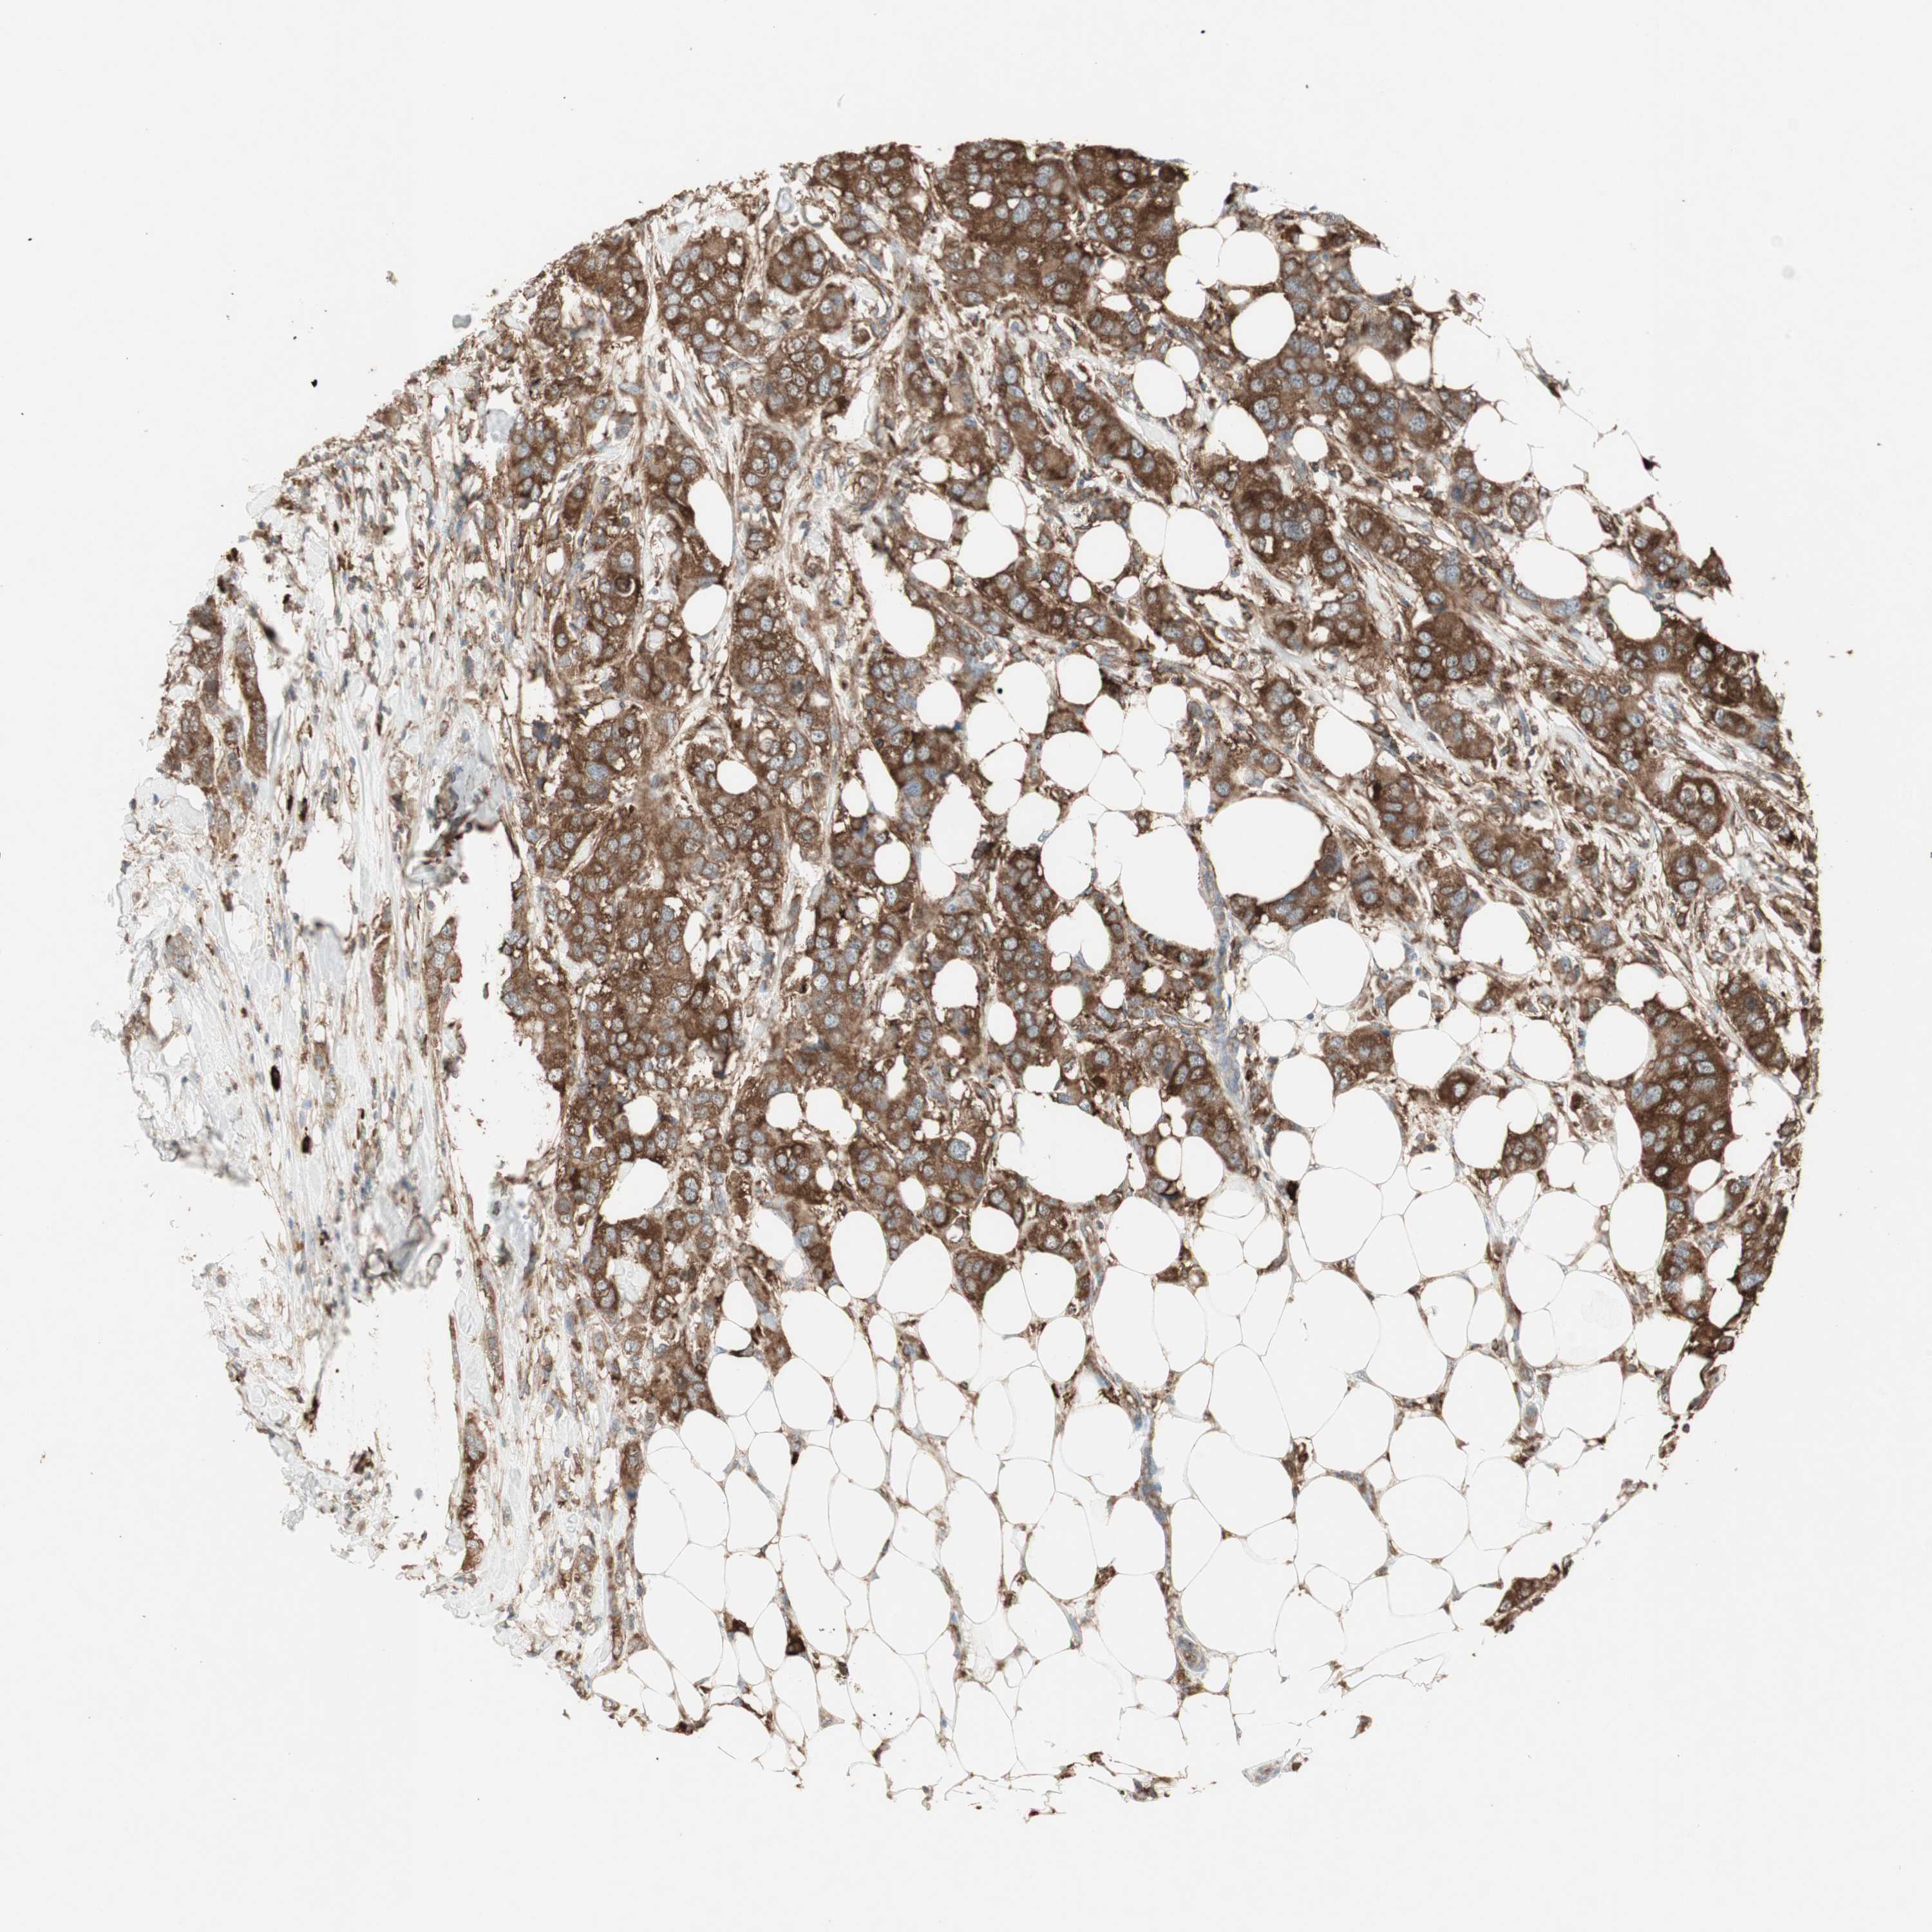

BRCA TCGA BRCA VALIDATION PROTEIN EXPRESSION